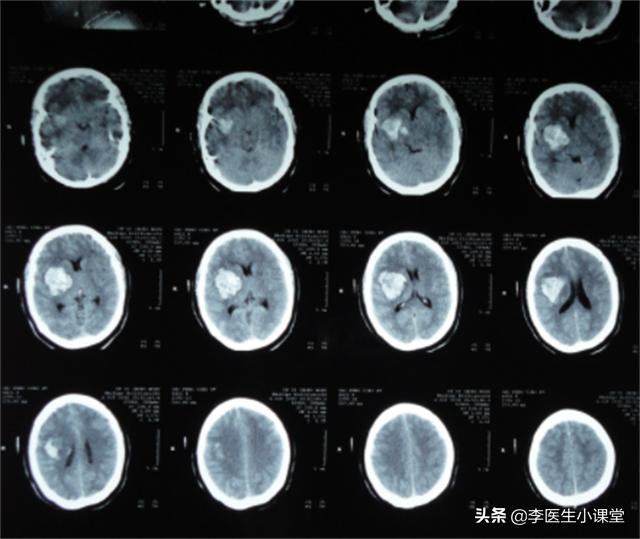

患者体温36.7℃、血压160/100、身高174cm、体重75kg。患者入院时意识模糊,无法正常沟通。颅脑CT显示:左侧基底节区脑出血(约15ml),双侧基底节区软化灶形成,可确诊为急性脑出血。